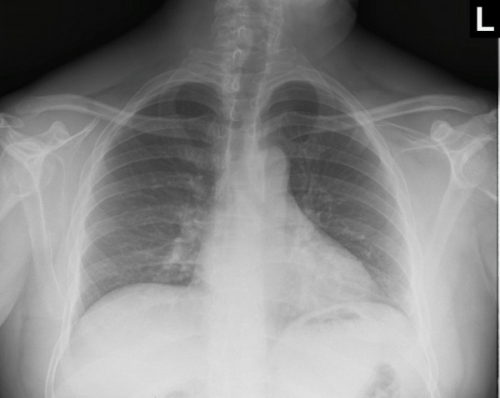

Tool to train medical student's eyes as to what a normal chest x-ray looks like, with over 500 consecutive normal images.